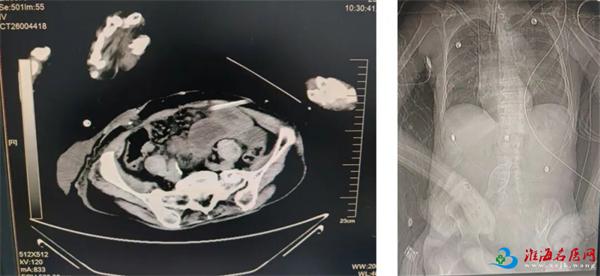

2026年1月9日,家住泉山区的91岁周大爷(化名),因腹痛1天,家人呼叫120送至徐州一院急诊医学科时,神志模糊,腹部压痛明显,腹部CT提示部分结直肠扩张积气,右下腹部分小肠积液,局部气液平,考虑肠梗阻。由于患者既往有脑梗、心功能不全、高血压、胸腔积液等多种基础疾病,经普外·胃肠外科、消化内科、呼吸与危重症医学科、心血管内科、神经内科、EICU多学科会诊后,收入EICU。EICU副主任徐杰、副主任医师时迎俊,给予患者灌肠、通便、扩肛等治疗。第一天患者逐渐排出少量干燥粪块,后继续积极给予导泻、调节益生菌、灌肠通便、启动滋养型肠内营养等综合处理,患者顺利解出粪便,腹痛缓解,肠道通畅,腹内压恢复正常,最终避免手术。